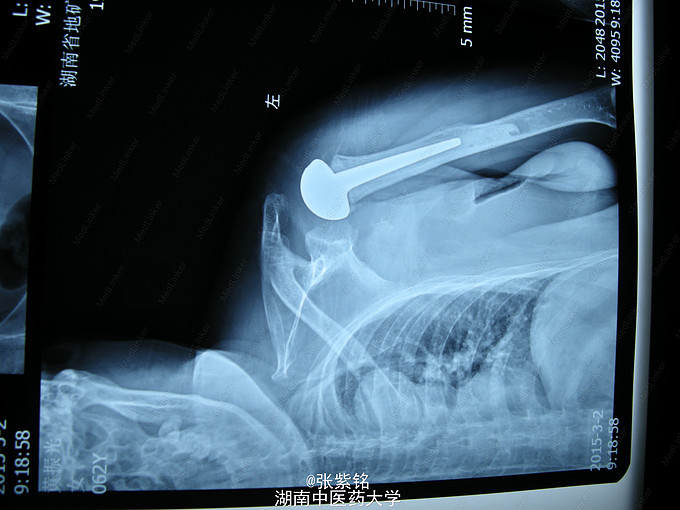

查体见:左额部可见约2cm*2cm皮下血肿,并可见一不规则伤口约2cm,伴活动性出血。脊柱驼背畸形,胸椎后凸,头部前伸体态;颈、腰部旋转活动不能,腰部于L3-5椎体棘突处压痛明显,双下肢肌力、肌张力正常。左肩部关节明显肿胀,可扪及空虚感;局部压痛明显,左Dugas征阳性,左肩关节主动上举,外展,后伸,内收活动受限;被动活动患处疼痛加剧,左侧桡动脉搏动可扪及,皮肤感觉正常,左肘、腕及各指间关节血运感觉活动正常。 X线片示:左肩关节脱位,左肱骨外科颈骨折,左肱骨大结节撕脱性骨折。

1、左肩关节脱位伴大结节撕脱性骨折,2、左肱骨外科颈骨折,3、头部外伤、头面部皮肤裂伤,4、强直性脊柱炎。 1、清创缝合伤口。2、患肢制动,消肿,止痛等对症处理。3、完善相关检查。4、择期行手术治疗及术后对症处理。